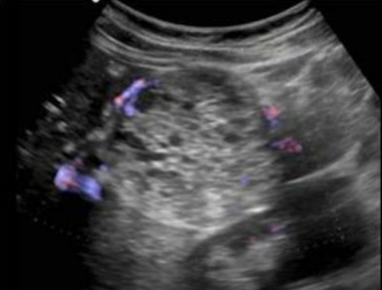

Describe this image

Dx?

An EUS image of a well-defined, hypoechoic cyst with a “central star” and microcysts/septations.

Dx: benign serous cystadenoma